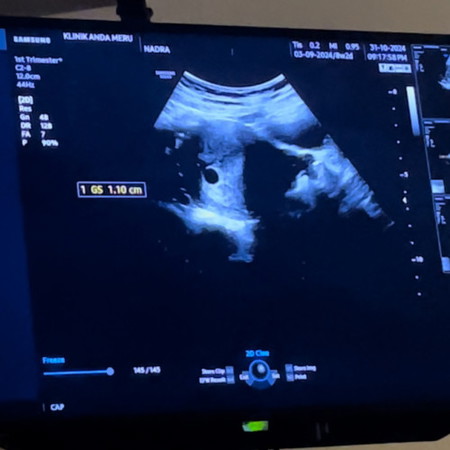

Blighted ovum

siapa ada masalah sama macam sy, ikut week dah 8w+ tp scan 6w+ .. nampak kantung je baby tak nampak.. doc suspek blighted ovum 😭 tvs dah buat still nampak kantung dan spotting on off 2 minggu dah.. tp sikit sikit je..

Just nak bg smgt kat sis.. kes kita serupa, sy try buat scan setiap minggu tak nampak2 kantung.. Sampai la masuk 8w, baru nmpk kantung n ukuran baru 6w. Baby takde. Doktor pun ckap mgkn blighted ovum. Sy tggu 2 mggu camtu bila scan baru la nampak baby. Tp heartbeat tkde. Next week sy pegi scan lg baru nampak heartbeat.. Dan ya ukuran kecik dari kiraan asal. Sy pun kerap sgt2 spotting n prnah dua kali bleeding mcm period. Tp alhamdulillah baby okay. Yg pnting kalau jd camtu kne trus gi emergency. Skrg sy masuk 10w nampak dh tgn kaki baby gerak2 kecik je.. inshallah sis bnykkan bed rest n masuk je mggu seterusnya, sis try cek scan lg ok.. jgn bnyk fkir nnt sis stress, pun bole jejaskan kesihatan sis dan baby

Baca lagisaya pon baru nampak kantung shj. kalau ikut LMP 8w, tapi scan nampak kantung ukuran baru 7w. dr suruh saya repeat scan lagi dua minggu. fikir yang positig je sis. in sha Allah ada tu untuk kita.